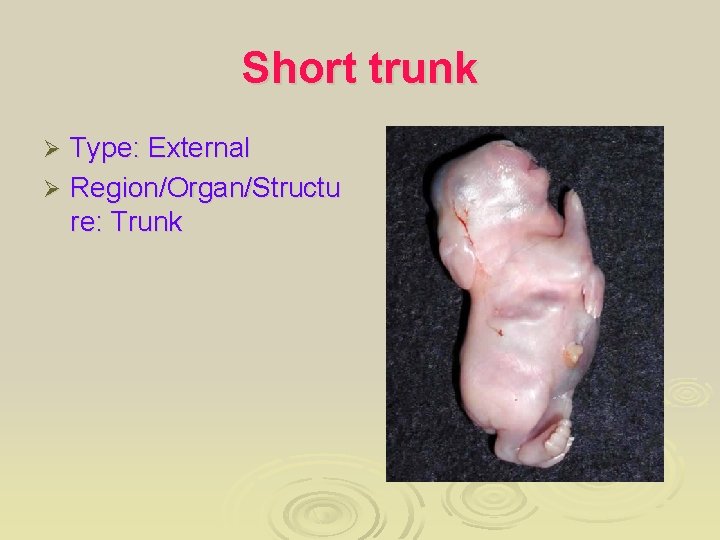

Short trunk Type: External Ø Region/Organ/Structu re: Trunk Ø